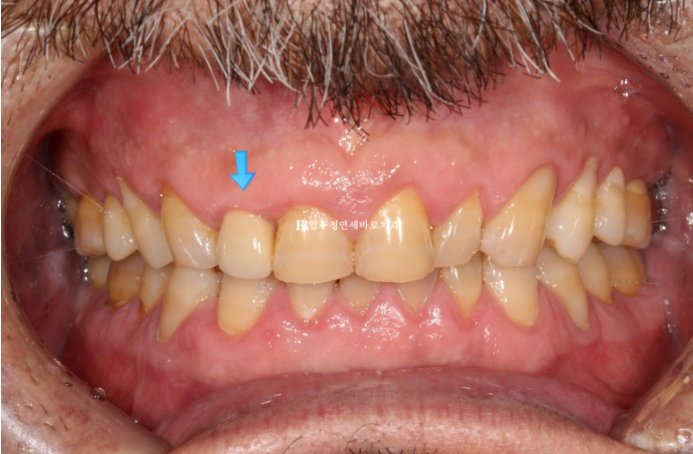

24.03

치아가 오랜 세월 마모로 인하여 짧아진 상태이며, 파란 화살표는 크라운 입니다.

배열이 가지런하면 말만 무삭제가 아니라 100% 무삭제가 가능합니다.

사실 배열이 가지런하지 않더라도 100% 무삭제 라미네이트는 가능합니다.

단

파란 화살표 치아가 뒤로 들어가 있으니 배열을 맞추기 위해서 두껍게 제작이 될 것 입니다.

장기적으로 치아와 잇몸건강을 해치게 되는 거죠